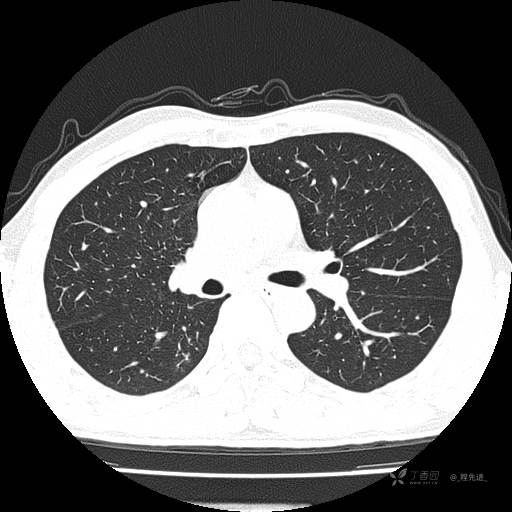

2月特别精彩病例|咳嗽、咳痰20余天,典型病例分享【结果已公布】

患者年龄:51岁

主诉:咳嗽、咳痰20余天

简要病史:20余天前开始出现咳嗽、咳痰症状,阵发性刺激性咳,白色粘痰,不易咳出,无发热,无咯血,无恶心、呕吐等不适,未诊治,咳嗽、咳痰症状持续存在。

体格检查:T:36.3 ℃ P:79 次/分 R:20 次/分 BP:128/64 mmHg,神志清楚,呼吸平稳,双肺呼吸音粗,右下肺闻及细湿性啰音。心率79次/分,节律整齐,各瓣膜听诊区未闻及病理性杂音。腹部未见异常,双下肢无水肿。

辅助检查:我院门诊胸部CT示:如下。心电图:窦性心律;正常心电图。